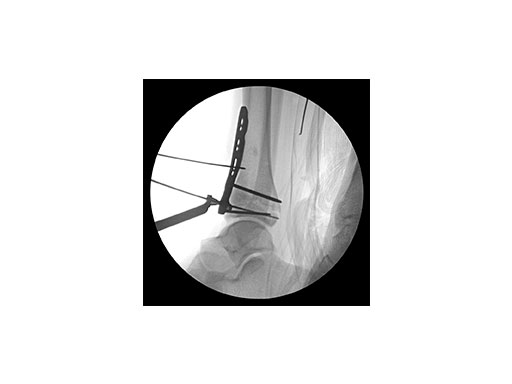

Surgeons performed an anterolateral surgical approach and distracted the joint using the distraction clamp and osteotome (Fig 2). The fracture was fixated with a VA-LCP Anterolateral Distal Tibia Plate (Fig 35).